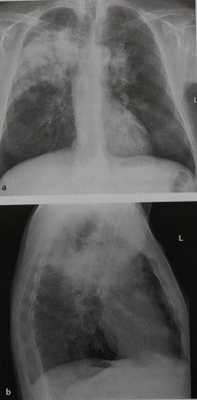

(Слева) На рентгенограмме органов грудной клетки в прямой проекции у пациента с гранулематозом с полиангиитом визуализируется большое объемное образование в правом легком, проецирующееся на правый корень. Картина крайне подозрительна на первичный рак легкого.

(Справа) На аксиальной КТ без КУ у этот же пациента в верхней доле правого легкого визуализируется опухолеподобный участок консолидации, представляющий собой подтвержденное очаговое поражение легкого при гранулематозе с полиангиитом. Такие образования могут быть единичными, также могут имитировать первичный рак легкого морфологически и при метаболических исследованиях (КТ и ПЭТ). (Слева) На аксиальной ПЭТ/КТ с ФДГ у этого же пациента определяется выраженное накопление ФДГ в объемном образовании. Характер метаболизма в данном образовании напоминает первичный рак легкого.

Гранулематоз Вегенера у мужчины 52 лет. Опухолевидная консолидация в верхней доле правого легкого. Аналогичные, но менее обширные инфильтраты имеются в другом легком.